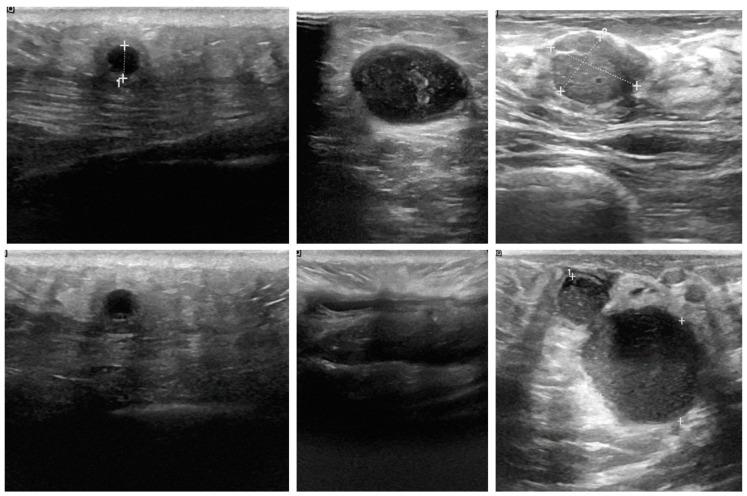

Breast cancer is a leading cause of mortality among women in Taiwan and globally. Non-invasive imaging methods, such as mammography and ultrasound, are critical for early detection, yet standalone modalities have limitations in regard to their diagnostic accuracy. This study aims to enhance breast cancer detection through a cross-modality fusion approach combining mammography and ultrasound imaging, using advanced convolutional neural network (CNN) architectures. Breast images were sourced from public datasets, including the RSNA, the PAS, and Kaggle, and categorized into malignant and benign groups. Data augmentation techniques were used to address imbalances in the ultrasound dataset. Three models were developed: (1) pre-trained CNNs integrated with machine learning classifiers, (2) transfer learning-based CNNs, and (3) a custom-designed 17-layer CNN for direct classification. The performance of the models was evaluated using metrics such as accuracy and the Kappa score. The custom 17-layer CNN outperformed the other models, achieving an accuracy of 0.964 and a Kappa score of 0.927. The transfer learning model achieved moderate performance (accuracy 0.846, Kappa 0.694), while the pre-trained CNNs with machine learning classifiers yielded the lowest results (accuracy 0.780, Kappa 0.559). Cross-modality fusion proved effective in leveraging the complementary strengths of mammography and ultrasound imaging. This study demonstrates the potential of cross-modality imaging and tailored CNN architectures to significantly improve diagnostic accuracy and reliability in breast cancer detection. The custom-designed model offers a practical solution for early detection, potentially reducing false positives and false negatives, and improving patient outcomes through timely and accurate diagnosis.

乳腺癌是台湾地区乃至全球女性死亡的主要原因之一。乳腺X线摄影和超声等非侵入性成像方法对早期检测至关重要,但单一模态在诊断准确性方面存在局限性。本研究旨在通过结合乳腺X线摄影和超声成像的跨模态融合方法,利用先进的卷积神经网络(CNN)架构来提高乳腺癌检测能力。乳腺图像来自公共数据集,包括RSNA、PAS和Kaggle,并分为恶性和良性组。采用数据增强技术来解决超声数据集中的不平衡问题。开发了三种模型:(1)与机器学习分类器集成的预训练CNN;(2)基于迁移学习的CNN;(3)用于直接分类的定制设计的17层CNN。使用准确率和Kappa分数等指标评估模型的性能。定制的17层CNN优于其他模型,准确率达到0.964,Kappa分数为0.927。迁移学习模型表现中等(准确率0.846,Kappa 0.694),而带有机器学习分类器的预训练CNN结果最低(准确率0.780,Kappa 0.559)。跨模态融合在利用乳腺X线摄影和超声成像的互补优势方面被证明是有效的。本研究证明了跨模态成像和定制CNN架构在显著提高乳腺癌检测的诊断准确性和可靠性方面的潜力。定制设计的模型为早期检测提供了一个实用的解决方案,有可能减少假阳性和假阴性,并通过及时准确的诊断改善患者的治疗结果。